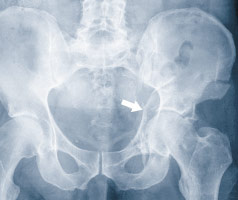

Abb. 2

b. Durch den Frakturspalt am Hüftgelenkspfannendach ist der Oberschenkelkopf sichtbar.

c. Hüftgelenkspfannendach mit den weggehaltenen grossen Gefässen zum Bein und dem Hüftbeugemuskel, den Gefässen und dem Nerv (gelb), die durch die Öffnung zwischen Schambeinast und Sitzbein verlaufen, und dem Samenstrang (violett).

Aufgrund der Tatsachen, dass das Hüftgelenk zwischen dem «Stoppa»-Zugang und dem Hautschnitt an der Beckenschaufel liegt und in der Wirbelsäulenchirurgie zur Behandlung von Frakturen an der unteren Lendenwirbelsäule ein Hautschnitt am äusseren Rand des geraden Bauchmuskels angewendet wird, entwickelte der Autor den «Pararectus»-Zugang für die Chirurgie der Hüftgelenkspfanne. Nach dem kleinen Hautschnitt von circa 10cm, im Gegensatz zum 30 bis 40 cm langen beim «ilioinguinalen» Zugang, wird die Hülle des geraden Bauchmuskels eröffnet. Anschliessend wird das Bauchfell auf der Innenseite abgeschoben und der Raum hinter dem Bauchfell dargestellt. Bei der weiteren Freilegung werden die Gefässe zur Bauchdecke und der Samenstrang respektive das Gebärmutterhalteband weggehalten (Abb. 2). Es folgt nun die Verschiebung der Hüftbeugemuskulatur und der Gefässe zum Bein. Dadurch wird der Blick auf den oberen Schambeinast und das Acetabulumdach frei. Bei der Darstellung des Hüftgelenkspfannengrundes von innen müssen die Gefässe und der Nerv, die zur Öffnung zwischen dem Schambein und dem Sitzbein verlaufen, geschont werden. Dieser minimalinvasive Zugang kombiniert die Vorteile des «ilioinguinalen» und des «Stoppa»-Zugangs. Erstmalig wurde der «Pararectus»-Zugang1 vom Autor im Dezember 2009 angewandt.